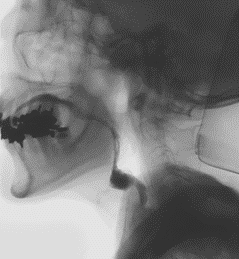

内視鏡的逆行性胆管すい管造影(ERCP)

内視鏡を口から挿入し、十二指腸にあるファーター乳頭と呼ばれる場所から造影剤を逆行性に注入し、胆管・すい管を造影して胆石や狭窄がないか調べる検査です。(胆膵造影検査ERCP等

20220309ERCP

ERCP : EndoscopicRetrogradeCholangioPancreatography